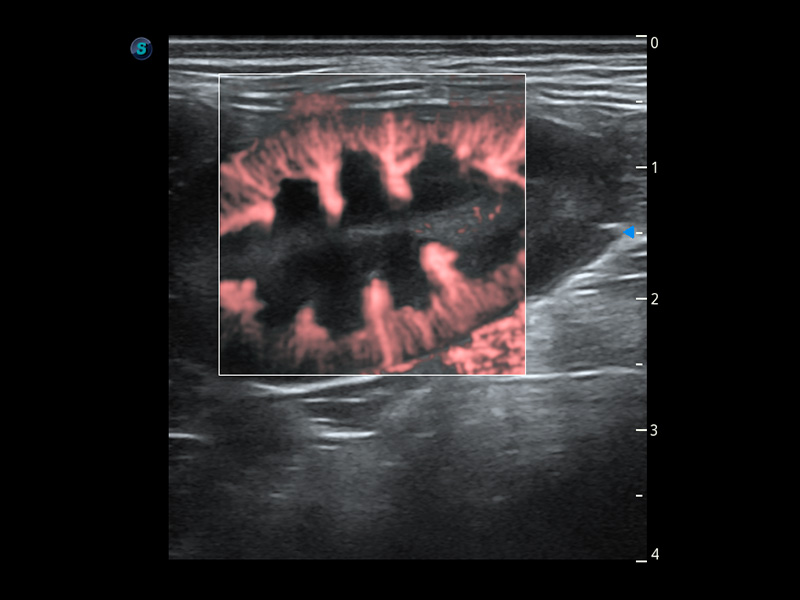

Bright Flow 立体血流成像

在传统二维血流成像的基础上,呈现血流的立体感,具有动感的生命力之美。精确区分不同血管的空间关系,提高了血流的视觉敏感性。

优异的基础图像

(犬)胆囊泥沙

(猫)膀胱结晶